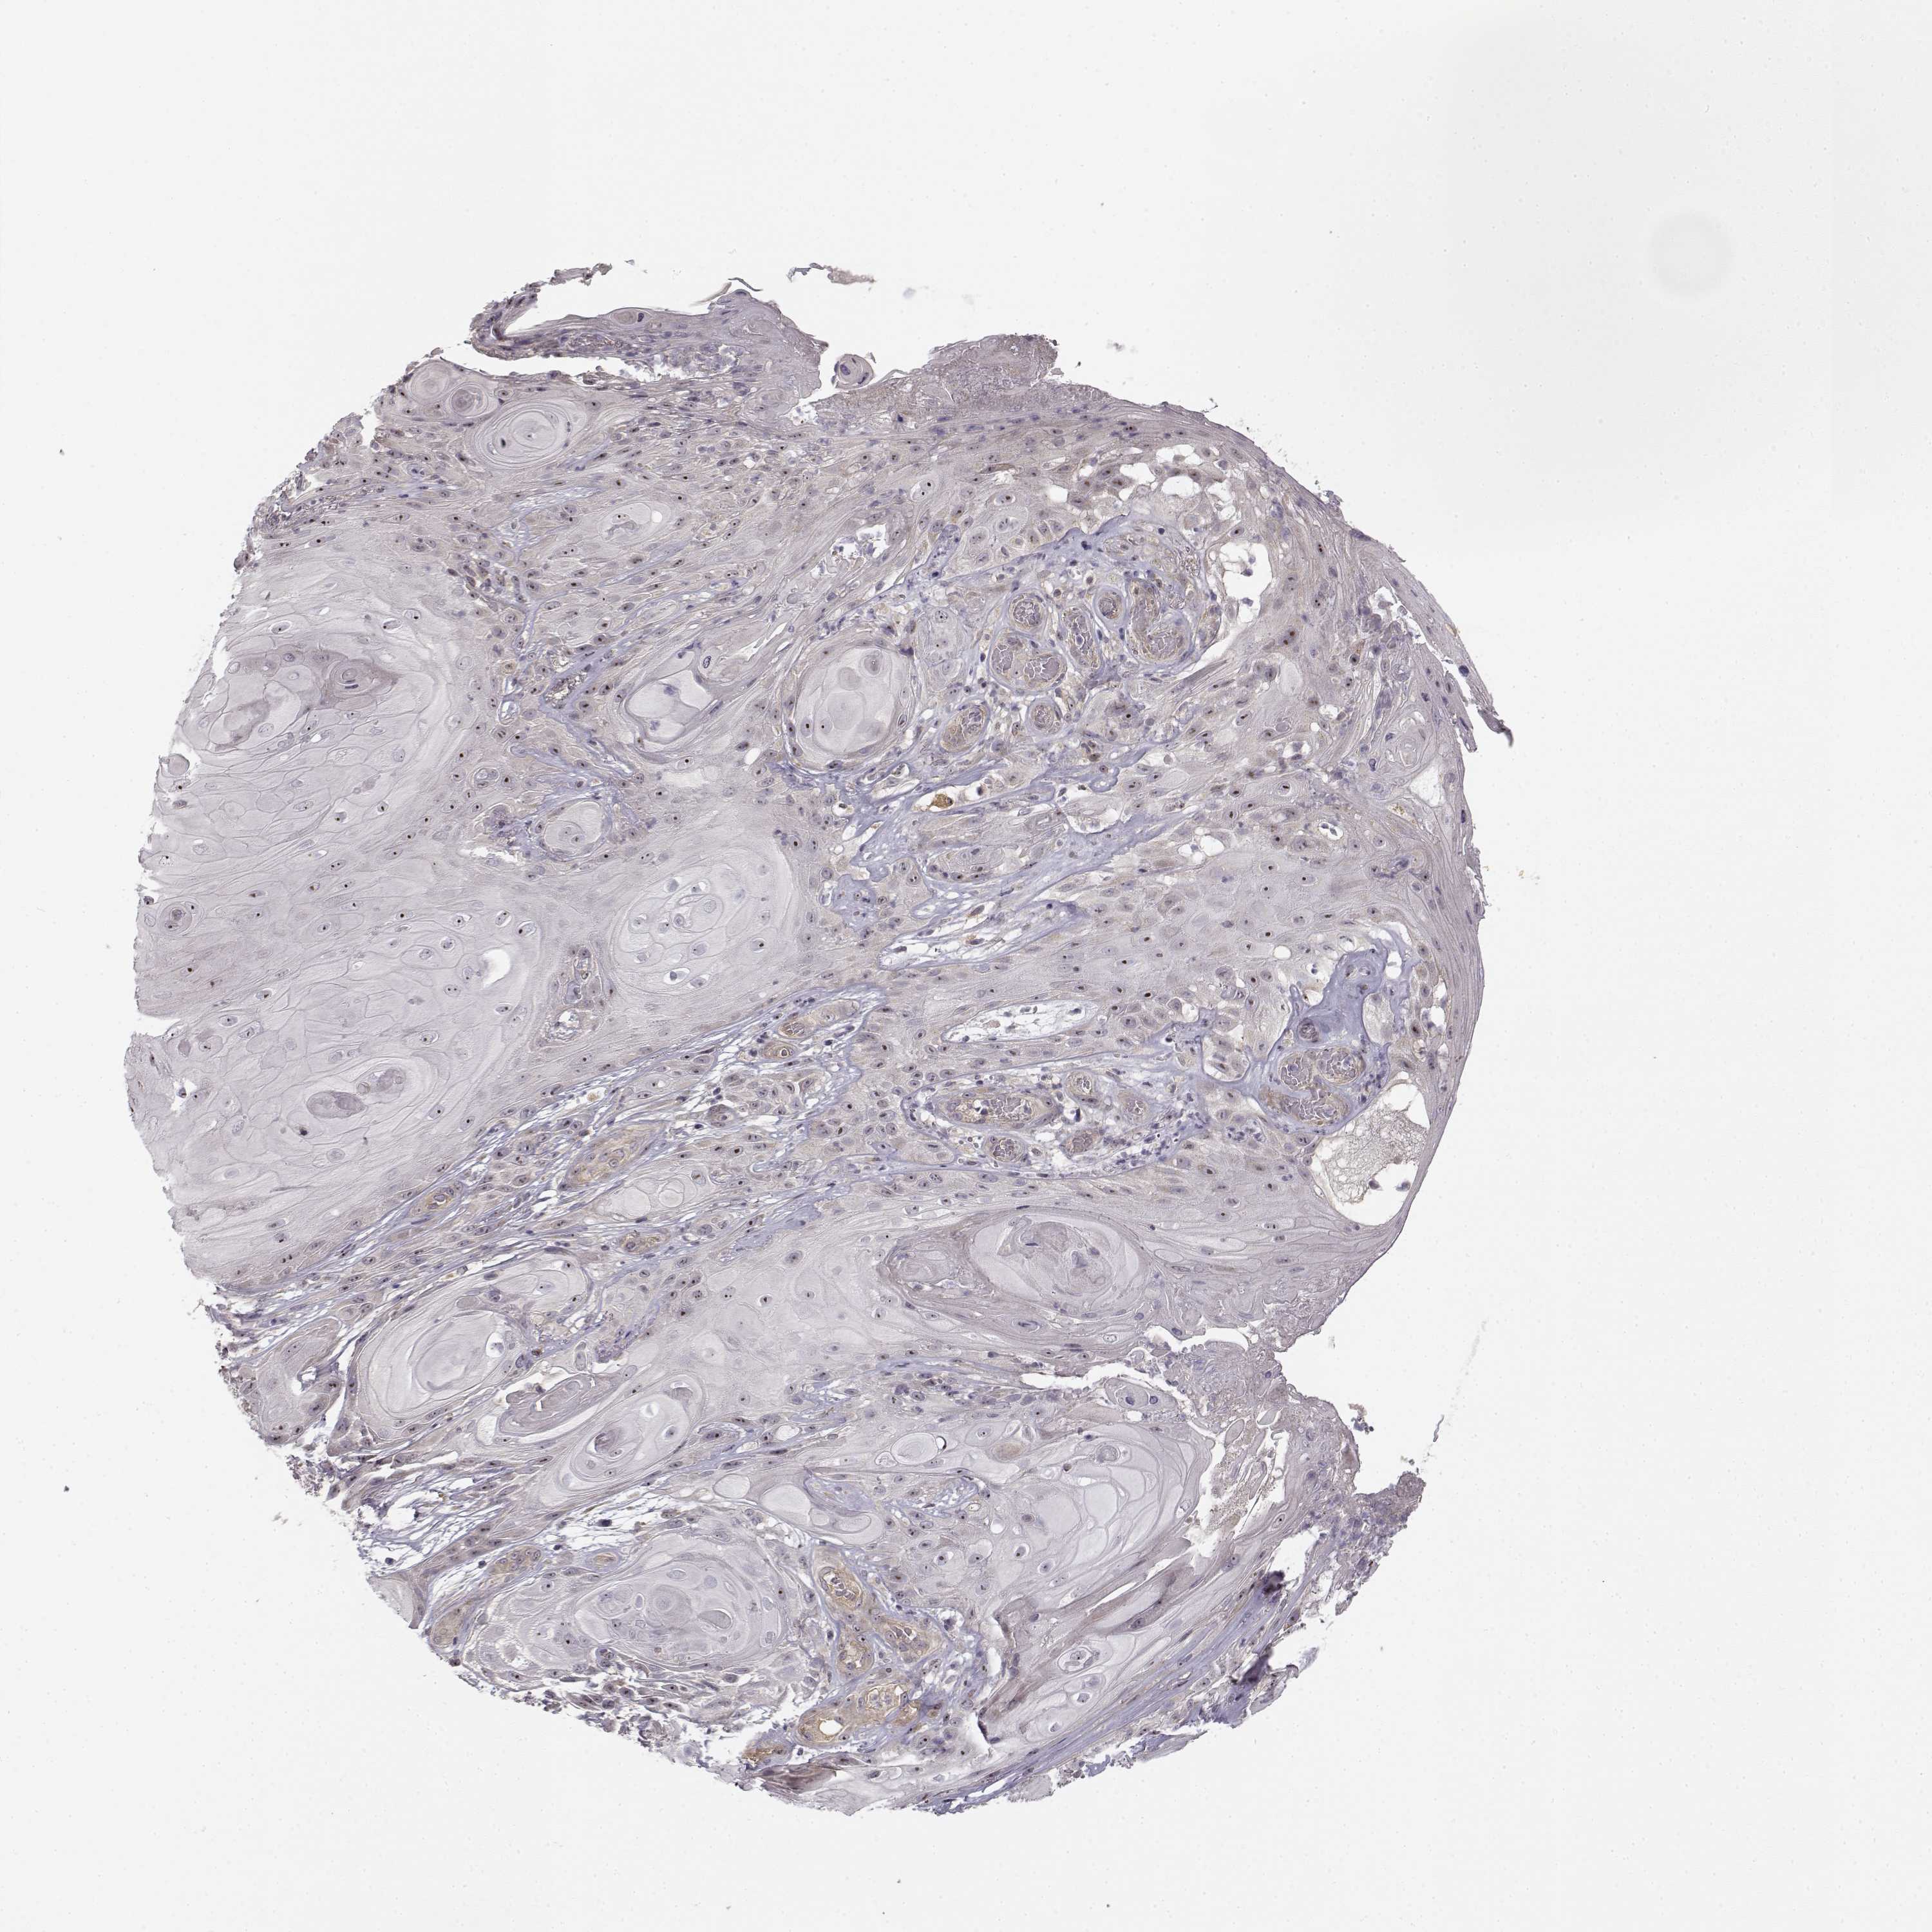

Basal cell and squamous cell cancer

SKIN CANCER - Protein expressioni

A mouse-over function shows sample information and annotation data. Click on an image to view it in a full screen mode. Samples can be filtered based on level of antibody staining by selecting one or several of the following categories: high, medium, low and not detected. The assay and annotation is described here.

Antibody stainingi

Antibody staining in the annotated cell types in the current human tissue is reported as not detected, low, medium, or high, based on conventional immunohistochemistry profiling in selected tissues. This score is based on the combination of the staining intensity and fraction of stained cells.

Each image is clickable and will lead to virtual microscopy that enables deeper exploration of all samples and also displays staining intensity scores, fraction scores and subcellular localization as well as patient and tissue information for each sample.

Antibody HPA036807

Staining

High

Medium

Low

Not detected

Intensity

Strong

Moderate

Weak

Negative

Quantity

>75%

75%-25%

<25%

None

Location

Nuclear

Cytoplasmic/membranous

Cytoplasmic/membranous,nuclear

Basal cell carcinoma

Squamous cell carcinoma, NOS